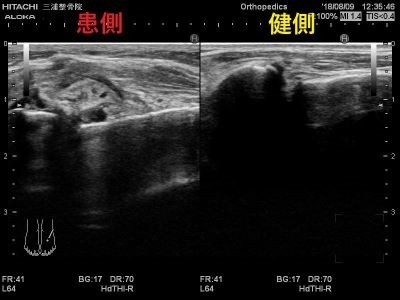

エコーではこのように写ります。

患側では大きく腫れて

正常な靭帯線維が見えないため

二分靭帯が断裂しています。